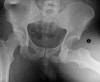

X-ray : 고관절 탈구(Hip anterior dislocation)

Pelvic AP, 무릎을 포함하여 Femur AP & lateral view 검사를 합니다. AP 사진상 정상골반에서는 대퇴골두의 관절간격의 크기가 대칭이며 같습니다.

뒤쪽 탈구시에는 손상 쪽 대퇴골두가 정상쪽으로 작아 보이며, 앞쪽 탈구시에는 손상 쪽이 더 큽니다. 절구 골절 동반도 흔하며(특히 뒤쪽벽), 이 경우 골절 유형 평가를 위해 CT 촬영을 합니다.